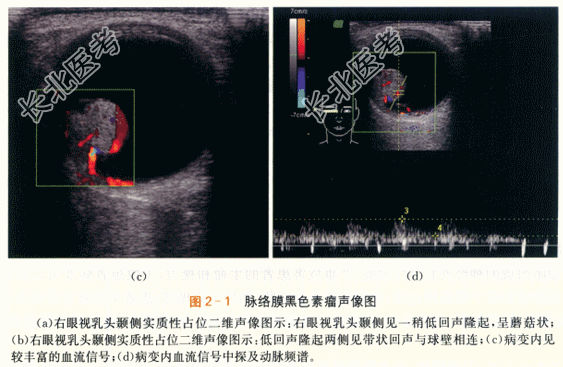

眼底检查示右眼玻璃体混浊。颞侧可见脉络膜实性隆起,呈棕褐色,表面有出血。隆起物周边视网膜呈青灰色隆起。

二、影像资料

- 简答题1、若患者诊断为脉络膜黑色素瘤,其声像图表现有哪些?